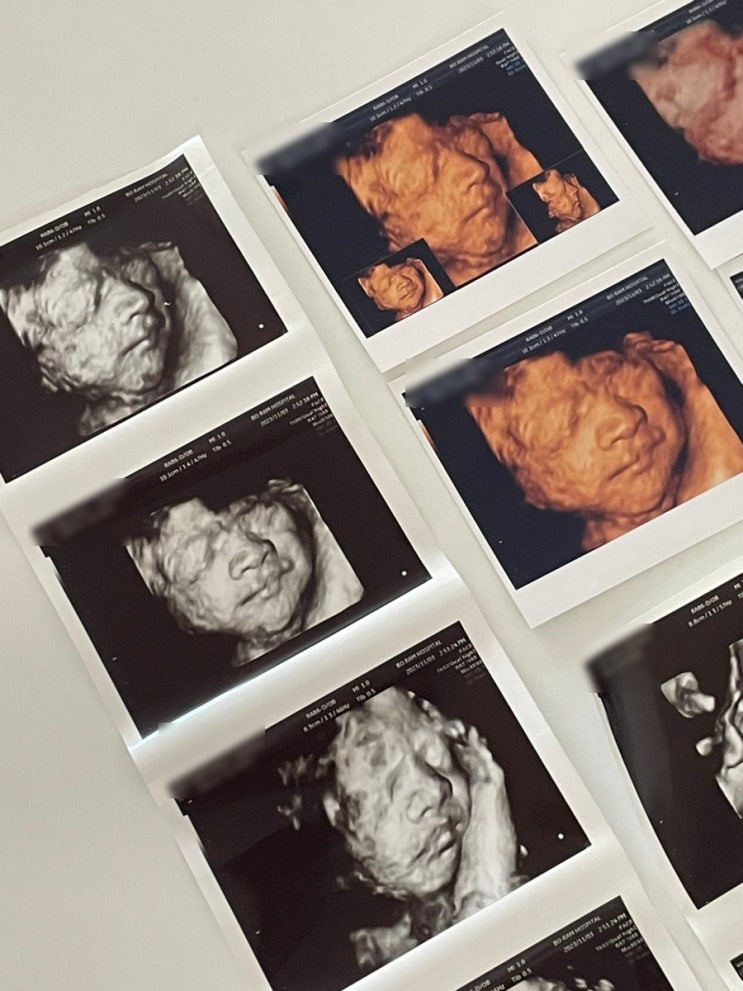

임신 27~30주 차 기록, 임당검사, 입체초음파 실패 그리고 성공, 베이비페이스 후기, 주수 배크기

시간이 왜 이렇게 잘 가는지 벌써 임신 후기에 접어드는 시기가 나에게도 찾아왔다..! 임당검사 후기, 입체...